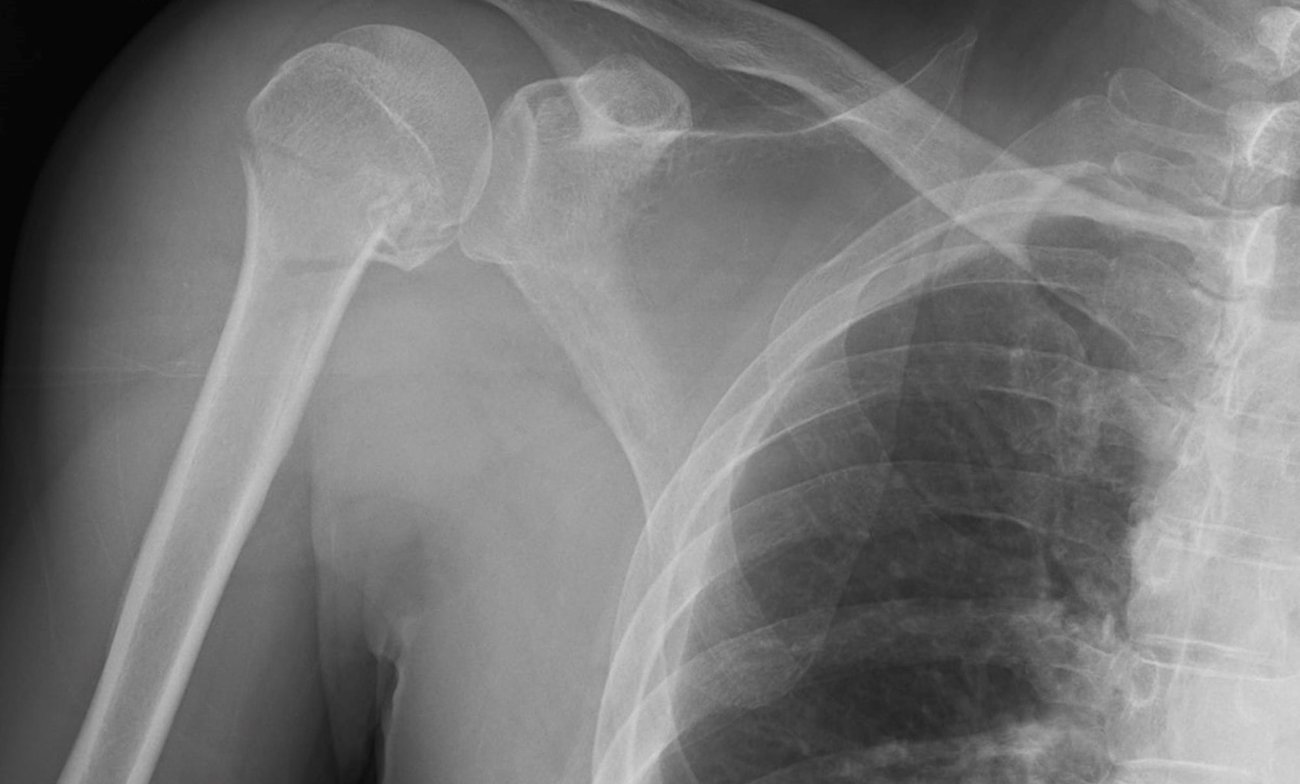

Neer 4-part proximal humerus fractures are surgically challenging, with a high risk of complications. Plate fixation, a common surgical approach for treating these types of fractures, may be supplemented with a bone graft to help increase fixation stability and healing rate. This study compared two types of grafting interventions: pectoralis major pedicle bone grafting and tricortical iliac grafting.

In this randomized controlled trial, 34 patients with Neer 4-part proximal humerus fractures were randomly assigned to receive either plate osteosynthesis with a vascularized pectoralis major graft (Group 1, n=17) or tricortical iliac grafting (Group 2, n=17). The primary outcome was reduction loss, and secondary outcomes included humeral parameters (humeral neck shaft angle, humeral head height, avascular necrosis) and functional assessments.

Group 1 experienced significantly less reduction loss (17.6% vs. 58.8%) and a lower incidence of humeral head avascular necrosis (5.8% vs. 29.4%) compared to group 2.

Patients in group 1 also demonstrated normal humeral neck-shaft angles in a higher percentage of patients and achieved satisfactory clinical and radiological results without introducing additional donor site morbidity.

Constant scores did not show statistically significant differences between the two interventions.

Bottom line. The use of a vascularized pectoralis major graft in plate osteosynthesis significantly reduces the risk of reduction loss and avascular necrosis of the humeral head compared with tricortical iliac grafting. Pectoralis major graft may be a valuable technique for achieving favorable clinical and radiological outcomes without imposing additional donor site morbidity.